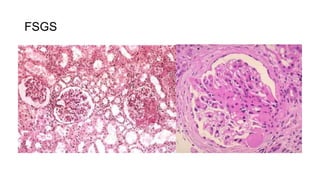

This document discusses several types of glomerular and interstitial kidney pathologies including acute post infectious glomerulonephritis, rapidly progressive glomerulonephritis/crescentic glomerulonephritis, focal segmental glomerulosclerosis, membranous glomerulonephritis, acute tubular necrosis/acute prerenal failure, acute pyelonephritis, and chronic pyelonephritis.